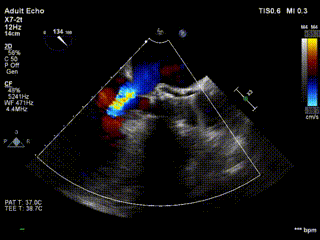

患者为86岁老年女性,左房增大,室间隔与左室后壁增厚。收缩期主动脉瓣瓣上流速5.4m/s,峰值压差117mmHg。超声提示主动脉瓣重度狭窄伴轻度关闭不全,二尖瓣轻度反流,三尖瓣轻度反流。

长短轴超声显示瓣膜形态良好,血流动力学良好